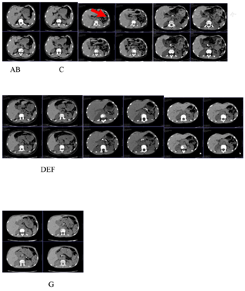

(5)影像学检查:上腹部CT:提示胰腺外形缩小,密度不均,可见数个斑片状结节状高密度影,胰管呈不规则串珠状扩张,示胰腺萎缩、钙化(图2)。

G为IIe)